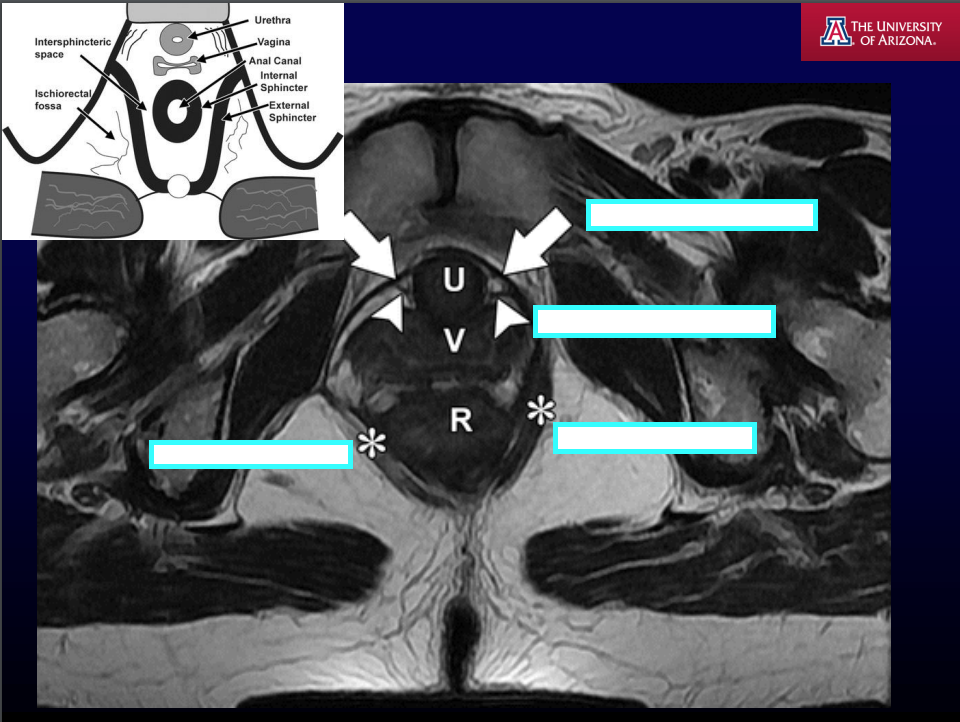

MRI T2WI fat is [] and fluid is [].

MRI T2WI fat is bright and fluid is bright.